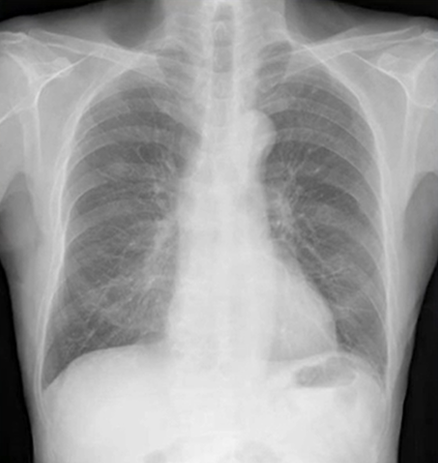

初期肺腺癌のレントゲン(X-p)写真

初期の肺癌の画像は読影がとても難しいです。「肺癌」を直接疑えなくても、異常陰影をとらえる、という順番で見ていくと「正常ではない」ことに気付け、精査へ進めます。今回は初期の肺癌画像です。分かるでしょうか?

所見としては右中肺野に限局したすりガラス影を認め、骨からはみ出てすりガラス陰影があることが分かります。このような限局性間瀬いつ性肺炎は存在しないため、精査が必要でCTに進むことが大切です。